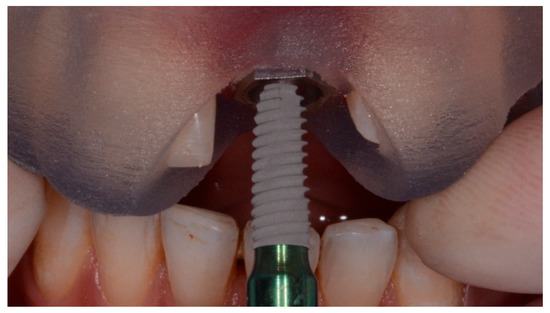

Figure 2.

Surgical template without metallic sleeves: Closed sleeves.